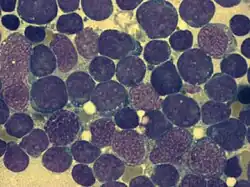

Bone marrow smear (large magnification) from a person with ALL

Bone marrow smear (large magnification) from a person with ALL -